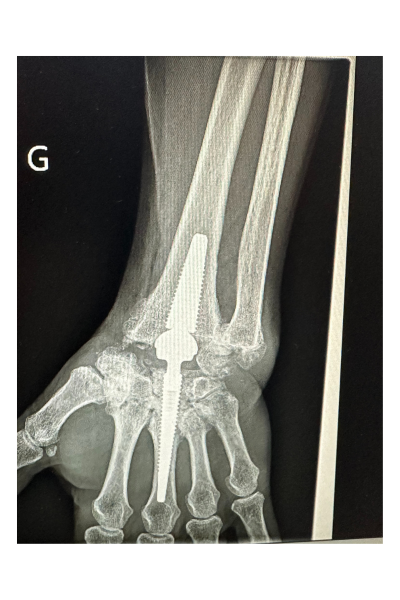

Pose de la 1ère prothèse de poignet de Roanne

Le Dr Ramy Belhaouane, chirurgien orthopédiste spécialiste du membre supérieur, pose la première prothèse de poignet de Roanne chez une patiente âgée de 63 ans.

Candidate idéale à l’intervention, la patiente de 63 ans du Dr Belhaouane a bénéficié d’une chirurgie innovante sur la région roannaise. En effet, la pose de cette prothèse de poignet lui permettra de traiter sa douleur et de garder de la mobilité, ce qui n’aurait pas été le cas avec une arthrodèse. Cette chirurgie innovante vient compléter l’éventail des traitements chirurgicaux que peuvent proposer les chirurgiens orthopédistes à leurs patients atteints d’arthrose. Ce traitement encore peu répandu (150 chirurgies en France en 2022) est pour le moment réservé à un profil limité de patient. Le candidat doit en effet répondre à un certain nombre de critères : âge, métier, type d’arthrose, localisation, absence de risque infectieux.

L’intervention nécessite un geste chirurgical précis dont la durée varie entre 1h et 1h30 et peut se réaliser en ambulatoire. Le chirurgien vient remplacer les os du carpe par une prothèse afin de restaurer une certaine mobilité articulaire.